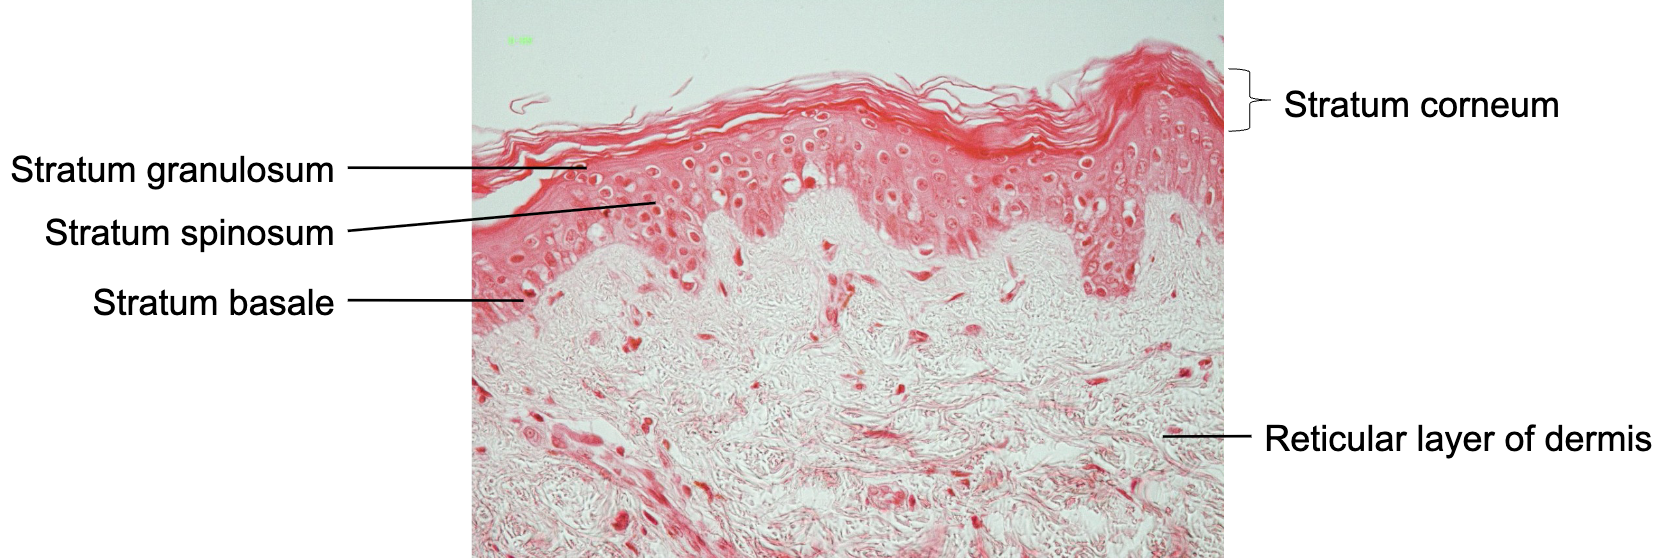

Label strata of epidermis

Thin skin: Strata of epidermis